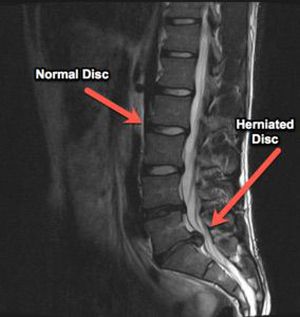

MRI showed herniated disc

It's extrusion of disc.